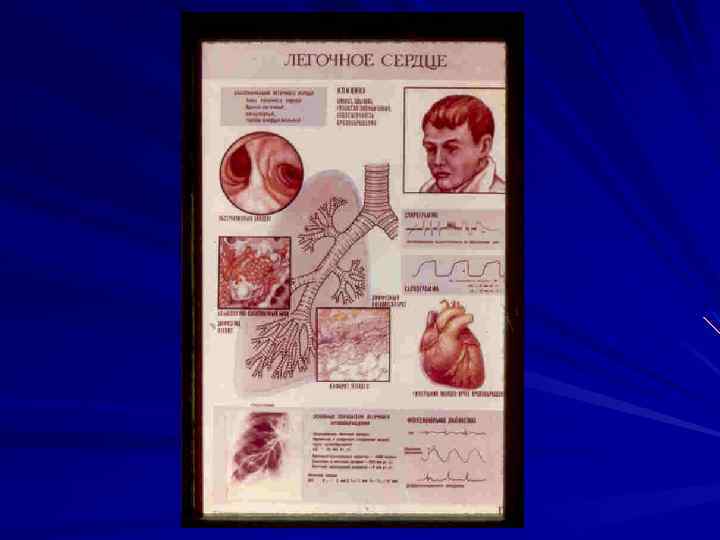

Легочное сердце (сor pulmonale). Определение – патологическое состояние, характеризующееся гипертрофией и (или) дилатацией правого желудочка сердца в результате легочной гипертензии, обусловленной первичными заболеваниями бронхолегочного аппарата, сосудов легких или торакодиафрагмальной патологией.

Классифицируется на: - острое легочное сердце; - подострое легочное сердце; - хроничекое легочное сердце. Стадии: - компенсированное - декомпенсированное (легочно- сердечная недостаточность).